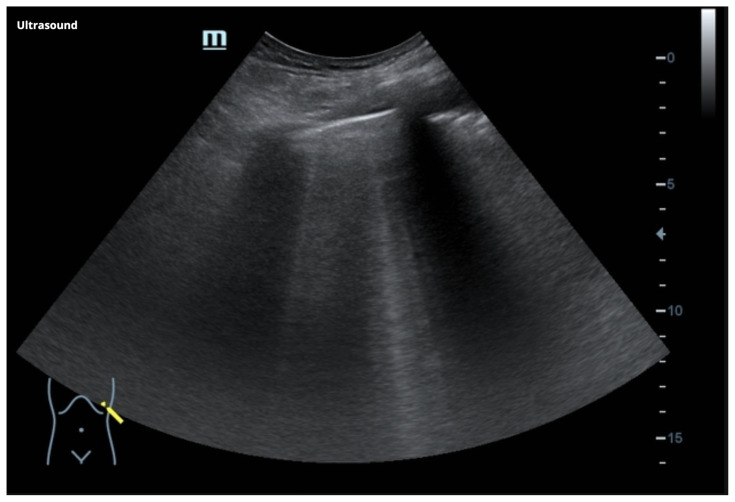

The learner should prioritize ordering a 12 Lead EKG and interpret it as Sinus Tachycardia with ST depression in the inferior lateral leads, recognizing that the patient’s EKG demonstrates a high risk for unstable angina or non-ST elevation MI. The learner may ask for an old EKG but no old EKG is available. The learner should order aspirin, either 162 mg or 325 mg. If the learner does not give immediately, the aspirin must be given before the end of the case. The learner also prioritizes ordering a portable CXR. The learner may choose to use the ultrasound at any time during the assessment to determine if the patient is in pulmonary edema. There is an ultrasound that is provided that demonstrates B-lines. Do not score down if the learner does not use the ultrasound though. The physical examination should be performed around this time. The learner also orders complete blood count (CBC), chemistry, troponin (high-sensitivity troponin is used in this case), B-Type Natriuretic Peptide (BNP), venous blood gas (VBG) or arterial blood gas (ABG). Once either the CXR or US has been done, the diagnosis of pulmonary edema should be made and the learner should order a diuretic and nitroglycerin. The learner may give sublingual nitroglycerin or just decide to administer IV nitroglycerin. Vital signs after sublingual nitroglycerin:

Stimulus #5

POCUS-Lung Ultrasound

Image Source: Botz, B. B-lines (ultrasound). In: Radiopaedia. https://doi.org/10.53347/rID-65567. CC BY-NC-SA 3.0